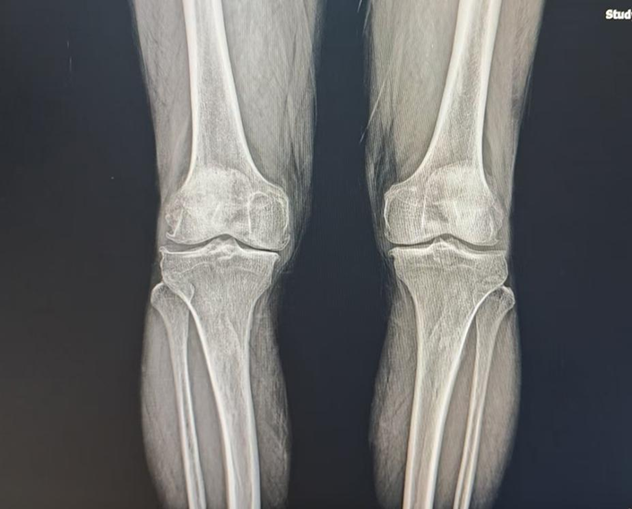

今年68岁的张大爷是山东临沂人,被膝关节骨性关节炎困扰了十余年。随着病情逐渐加重,他的双膝疼痛愈发剧烈,不仅行走困难、蹲起受限,关节还出现了明显变形,形成了“O”型腿,严重影响了晚年生活质量。为了摆脱病痛、恢复关节功能,重新拥有正常的行走能力,张大爷下定决心接受手术治疗。